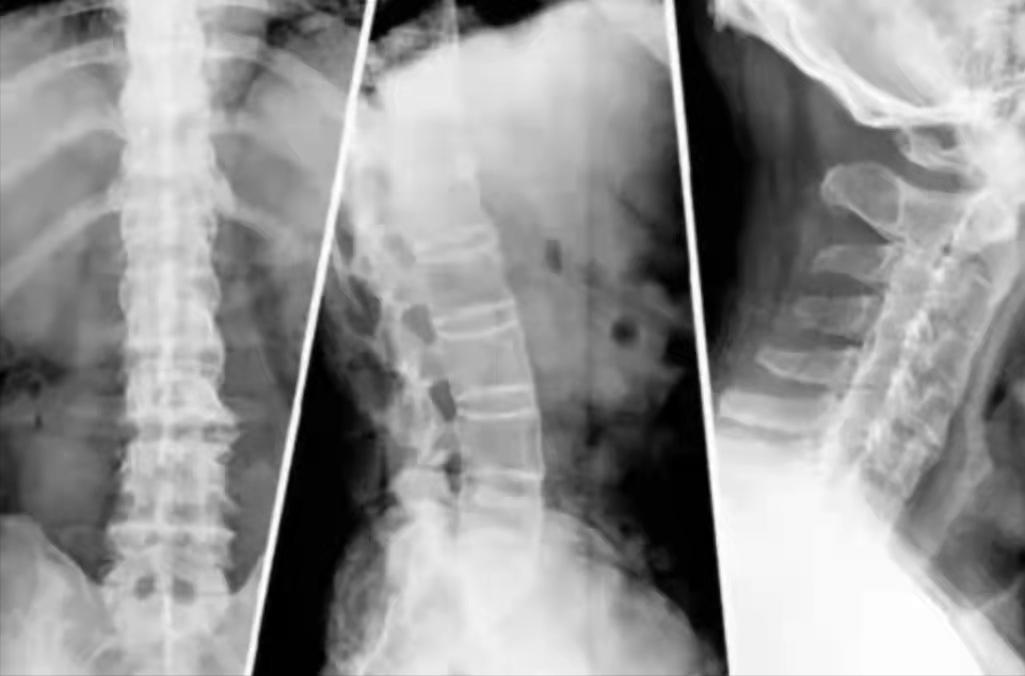

强直性脊柱炎主要通过实验室检查来确诊,一般常见的是骶髂关节X线片、CT、核磁共振以及HLA-B27检测、红细胞沉降率(又称血沉)和C反应蛋白等检查。

另外,还可以通过脊柱CT、核磁共振的方法均能观察骶髂关节的病变,并作出深入的观察。总之,这两项检查也是确诊强直性脊柱炎的一个重要诊断依据。